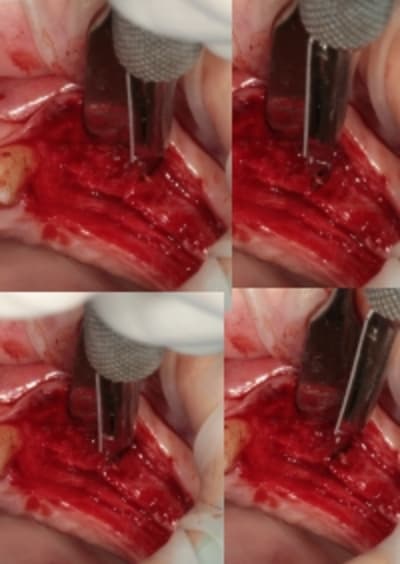

quand je fais du deux temps (expansion, comblement avec du biomat et intervention c'est parce que l'os est à sa limite et ne peut gérer une reconstruction et une ostéo-intégration.

Il s'agit alors d'os D1 ou de crête d'environ 1mm.

exemple:

le cas que je présentes pour René: 3 implants pour 3 bonnes heures.

Mais pas de greffe et vraiment en live un résultat qui me comble de bonheur, l'os était "adorable" et se pliait à mes demandes...Que du plaisir.